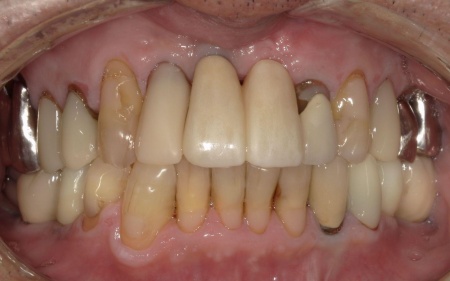

70代男性 右下奥歯を抜いてインプラント治療で噛み合わせを回復した症例

「2週間ほど前から、右下奥歯の歯茎が腫れている」とご相談いただきました。

拝見したところ、右下奥歯(第2小臼歯)の周辺組織に炎症が広がり、歯茎が赤く腫れていました。

このまま放置すると、さらに炎症が広がって周囲の歯茎や骨に悪影響が出たり、痛みが強くなったりするリスクがあります。

以上のことから、早急に治療をする必要があると診断しました。